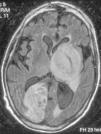

Paciente 5Varón de 56 años afectado de DM, CI y neoplasia de recto en tratamiento quimioterápico, que presentó un cuadro brusco de hemianopsia homónima izquierda. La TC craneal simple mostró una imagen hipodensa occipital derecha, orientándose el cuadro como tumor metastásico frente a infarto occipital. La RM craneal apoyó el diagnóstico de lesión isquémica. Una semana más tarde, el paciente presentó hemiparesia derecha, disartria y febrícula, sin signos meníngeos. En la analítica general destacaba una linfocitopenia. La TC craneal mostró una nueva imagen ganglionar basal izquierda compatible con un infarto reciente. El paciente evolucionó mal, con disminución del grado de consciencia y aparición de una nueva focalidad neurológica. La RM craneal mostró imágenes supratentoriales bilaterales con captación de contraste en anillo e importante efecto de masa, compatibles con abscesos múltiples (fig. 1). En un hemocultivo que se practicó por febrícula persistente creció L. monocytogenes. Se inició un tratamiento con ampicilina y gentamicina, a pesar del cual el paciente falleció 50 días más tarde. El TDT fue de 12 días.

En cuanto a los estudios de neuroimagen, ya en el caso de los abscesos de tronco por Listeria se había descrito la superioridad diagnóstica de la RM craneal respecto a la TC craneal62. Sólo en uno de los 6 pacientes de este estudio se emitió un diagnóstico inicial de absceso piógeno mediante la TC craneal simple, mientras que el diagnóstico de absceso se indicó mediante RM craneal o TC craneal con contraste. Se puede inferir, por tanto, que en los abscesos cerebrales por L. monocytogenes la RM craneal y la TC craneal con contraste son un método diagnóstico mucho más fiable que la TC craneal simple. Como ya se había descrito en otras revisiones, la localización en ganglios basales y tronco encefálico y la presencia de múltiples abscesos es más frecuente en los abscesos por Listeria que en el resto de los abscesos piógenos. Esto puede explicarse por el mecanismo de invasión exclusivamente hematógeno de L. monocytogenes, a diferencia de un importante número de abscesos piógenos que son secundarios a un foco contiguo de infección por otros gérmenes45. También en estos casos se cumple esta circunstancia, dado que 4 de los pacientes de este estudio presentaron múltiples abscesos bilaterales (2 pacientes) o microabscesos de tronco (2 pacientes).